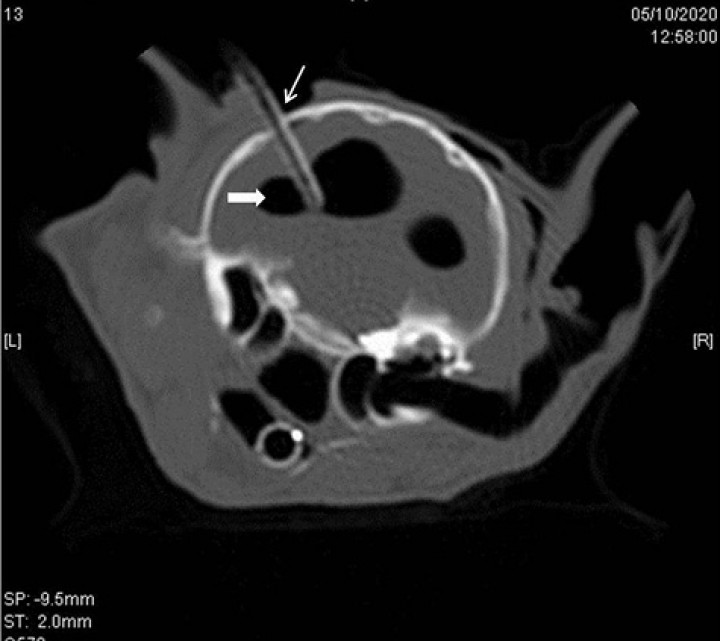

Corte transversal en algoritmo de hueso de 2 mm de grosor a la altura de las bullas timpánicas del TAC postoperatorio en el que se muestra el catéter intraventricular (flecha) en el ventrículo lateral izquierdo, el cual se muestra dilatado, con márgenes bien definidos, redondeado e hipoatenuante (flecha sólida), igual que el ventrículo lateral derecho pero este en menor cantidad.